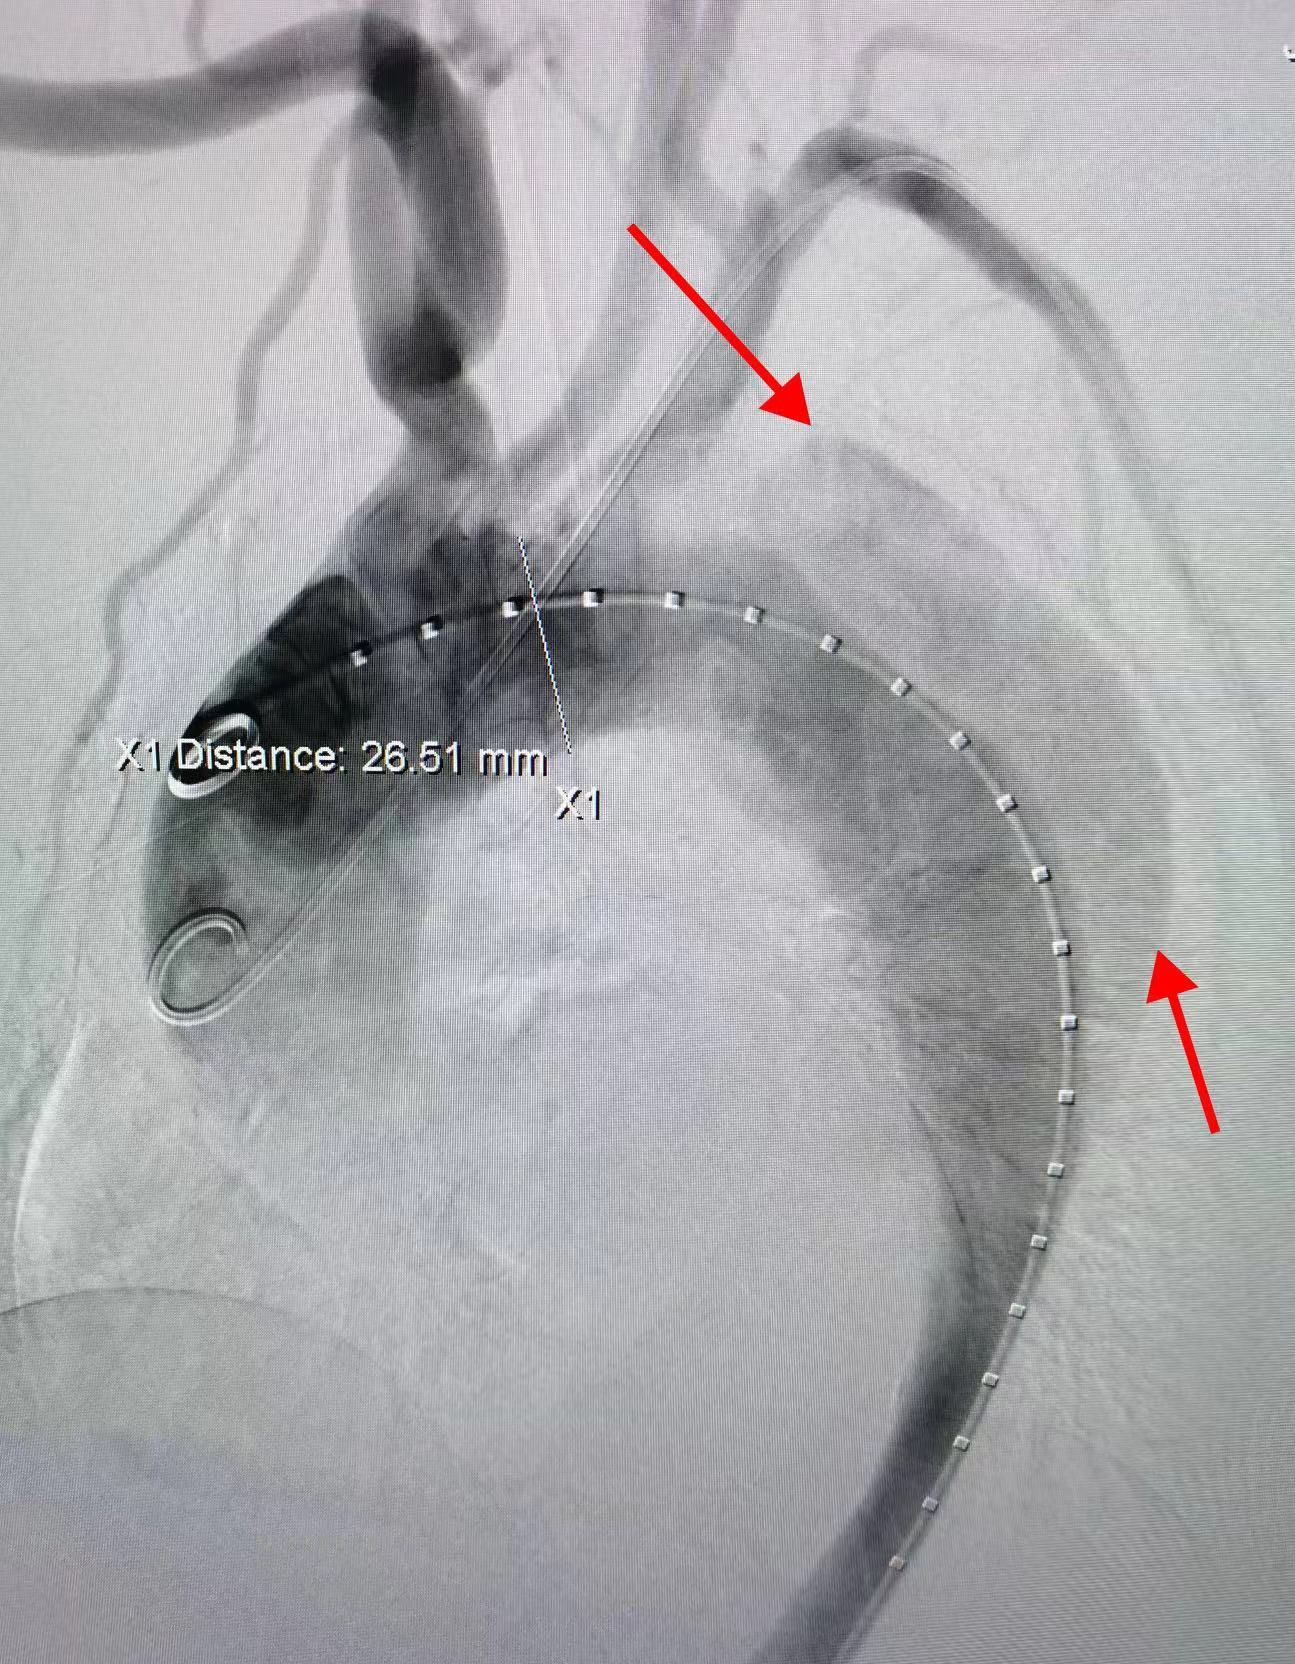

術(shù)中造影可見夾層。

經(jīng)過主動(dòng)脈CTA 檢查,發(fā)現(xiàn)王女士主動(dòng)脈距離降主動(dòng)脈一公分左右有破口撕裂,確診為B型主動(dòng)脈夾層。

然而,病情的復(fù)雜程度超乎想象。由于假腔破口離左上肢供應(yīng)血管距離近,如果貿(mào)然植入支架可能會(huì)導(dǎo)致鎖骨下動(dòng)脈血流不暢,影響左上肢活動(dòng)。治療主動(dòng)脈夾層的同時(shí)如何保護(hù)左側(cè)鎖骨下動(dòng)脈便成了治療的一個(gè)關(guān)鍵點(diǎn),必須精準(zhǔn)平衡,缺一不可。

心胸大血管外科副主任錢海云接診后,仔細(xì)查看了患者的檢查結(jié)果,在深思熟慮與團(tuán)隊(duì)的多番研討后,確定了治療策略:放雙支架打通 “生命通道”。這一方法可封閉主動(dòng)脈的夾層撕裂口,也可以重塑鎖骨下動(dòng)脈,達(dá)到血運(yùn)重建的目的。

經(jīng)股動(dòng)脈血管成功將覆膜支架植入患者胸主動(dòng)脈以閉合夾層破口。同時(shí)準(zhǔn)確定位左鎖骨下動(dòng)脈開口并植入一根平行支架。多角度定位后,支架順利釋放,至此主動(dòng)脈破口得到完全封堵,主動(dòng)脈真腔及左鎖骨下動(dòng)脈重建完畢。術(shù)后,王女士恢復(fù)良好,第二天已經(jīng)能夠正常下床活動(dòng)。